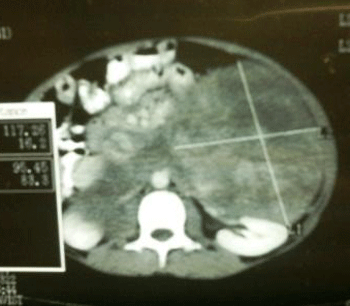

A 10-year boy presented with a painless swelling in the left upper abdomen which gradually increased in size. Physical examination revealed a non tender, smooth, firm and an irregular mass in left hypochondrium extending to left lumbar region. On ultrasound, a hypoechoic lesion (14cm x10cm) in left suprarenal region was noted. Computed tomography (CT) revealed a large (18cm x 12cm) lobulated hypodense lesion with linear hyperdense enhancing areas in the left suprarenal region (Fig. 1). The lesion displaced the stomach and pancreas anterio-superiorly, the left kidney posterio-inferiorly and the spleen laterally. The fat planes surrounding these structures were intact. There was stretching of the splenic and left renal veins. Medially, the mass was seen extending anterior to the abdominal aorta. There was anterio-lateral displacement of the portal vein and inferior vena cava while the bowel loops were displaced inferiorly.

Figure 1: CT scan abdomen. |